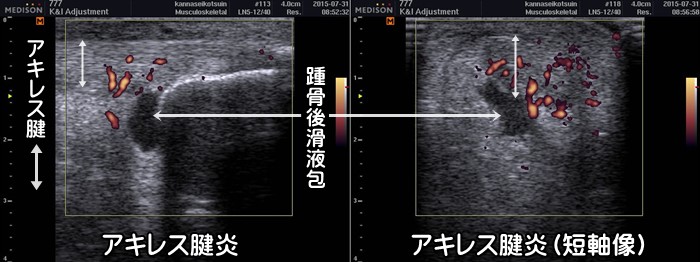

急性アキレス腱炎

急性のアキレス腱炎では踵骨後滑液包の水腫と著明な血流信号がみられます。

痛風や関節リウマチでも同様の症状がみられます。